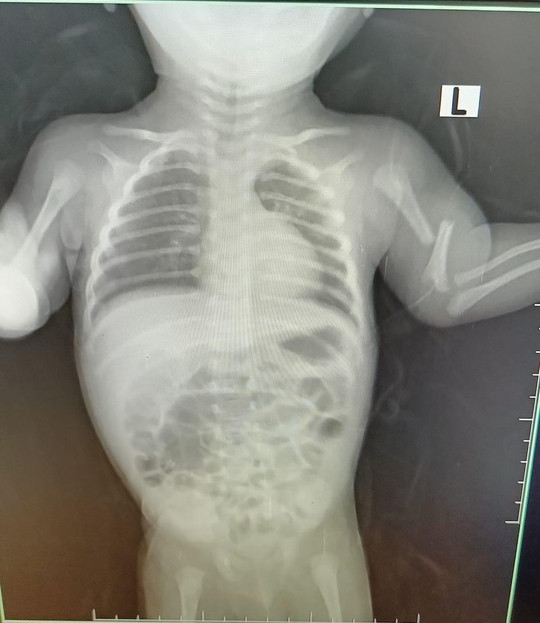

| Ảnh chụp phim cho thấy xương tay cháu bé gãy nhiều phần. |

Trước khi xảy ra vụ việc vào ngày 15-8 thì từ 17-7, cháu B. đã phải nhập viện Nhi Đồng 2 (TP HCM) với chẩn đoán xuất huyết dưới màng cứng bán cầu não phải, gãy hở 1/3 giữa xương đùi trái, gãy cũ xương cánh tay 2 bên, gãy xương sườn số 7 bên phải, viêm xương, viêm mô tế bào vùng cổ, viêm phổi nặng, nhiễm trùng huyết, suy dinh dưỡng nặng.

Tại khoa cấp cứu, cháu bé có biểu hiện lừ đừ, tiếp xúc chậm, co gồng tay chân.

Tổng trạng suy kiệt, môi hồng, chi ấm, mạch rõ, thở co lõm ngực… nhiều vết trầy xước da mặt, cổ, tay 2 bên, biến dạng tay trái, gãy hở xương trái đang nẹp cố định.

Đến sáng 31-7, cháu được mẹ làm thủ tục xuất viện với chẩn đoán viêm phổi, nhiễm trùng huyết, gãy đa xương, vết thương phần mềm, xuất huyết não.